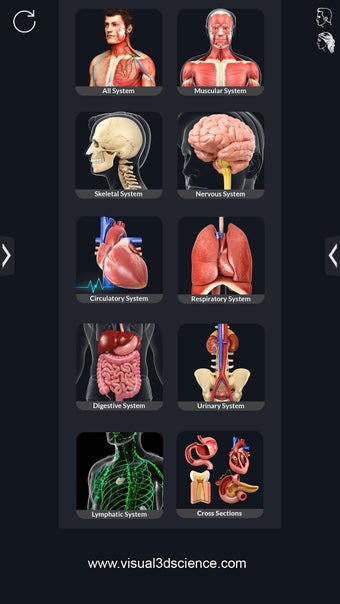

¿Qué ofrece la aplicación?

Puedes seleccionar cada parte del cuerpo por separado para ver su nombre o leer información relacionada. Puedes ocultar y mostrar cada parte del cuerpo, así como rotar 360° alrededor de un modelo 3D altamente realista. Puedes dibujar en la pantalla o compartir capturas de pantalla con tus amigos. Puedes encontrar la definición de cada parte del cuerpo y su anatomía.